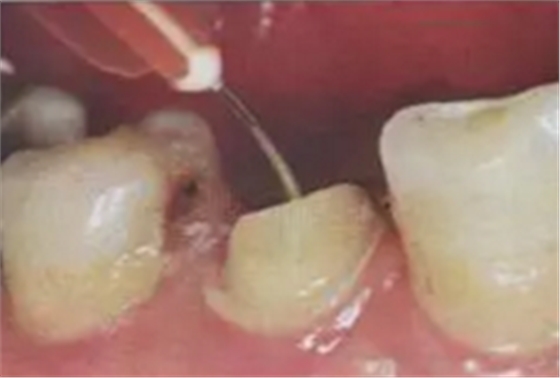

11. 吸取根管內(nèi)多余的粘結(jié)劑

根管內(nèi)涂抹粘接劑時(shí),理想的粘接劑層厚度為25um - 40um,厚度增加或不均勻不利于纖維樁的順暢就位,多余的粘接劑的存在會(huì)加速樹脂水門汀的固化速度。

(粘結(jié)劑涂擦20s,涂抹2-3層)

(紙尖吸出多余粘結(jié)劑)

根管內(nèi)涂抹粘接劑的較規(guī)范操作應(yīng)是:毛刷蘸取粘接劑在根管內(nèi)反復(fù)涂擦20s,涂抹2-3層,然后用紙尖吸取干凈,氣槍吹5s使粘接劑中的溶劑快速揮發(fā)。此操作中,大錐度吸潮紙尖非常關(guān)鍵,它不僅可以吸取多余的粘接劑,同時(shí)也可使粘接劑在根管內(nèi)鋪展均勻。醫(yī)生朋友不要“忽視小物件鑄成大事件。